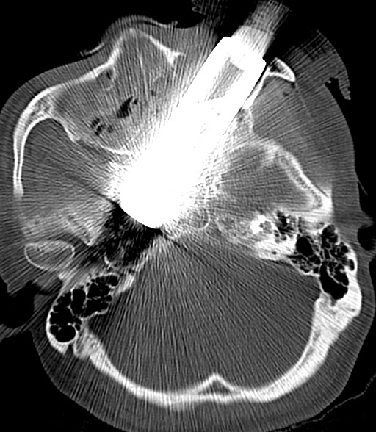

患者,男,31岁

外伤致左眼出血、疼痛4小时余入院

NS:神清,对答好,左侧眼内容物缺失,左上眼睑可见长约4cm外伤伤口,眼内可见金属异物,右侧瞳孔直径3mm,对光反射正常,眼前2m指数;四肢活动可,肌张力正常,生理反射存在,病理反射未引出。

2014-9-29 CT

介入手术:(缺Fagarty /Merci/ Penumbra球囊导管、带膜支架)颈内动脉颅内外段置球囊保护,拔异物。

问题:1、颈内动脉破裂处理?2、取栓再通,如何防止血栓脱落?